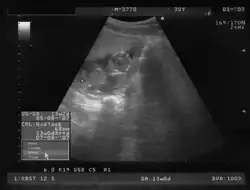

Ecografía de 12 semanas -

Los signos positivos de certeza de un embarazo consisten en poder demostrar sin error la presencia de estructuras embrionarias mediante ultrasonido y otras imágenes radiológicas.

Rastreo ecográfico

En cualquier momento del embarazo, en especial en presencia de un feto maduro en la segunda mitad del embarazo, es posible demostrar por ecografía transabdominal bidimensional o tridimensional tanto sus partes anatómicas como el saco vitelino.